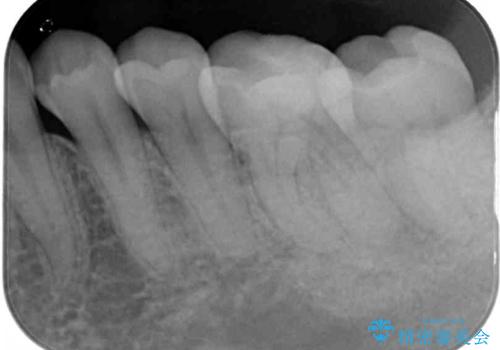

- 近医にてセラミックを装着した左下の奥歯に痛みが続いたとのことで来院された患者様です。

診査の結果、既に歯の神経は失活していたおり、排膿路が認められ、叩いたり触ったりしたときの痛みも確認されました。

根管治療を行った後にオールセラミッククラウンにて補綴することとしました。

初回の治療後には歯肉に認められた排膿の出口などの症状は消えていました。

補綴後6ヶ月経過しレントゲンを撮影したところ、遠心の歯根付近の病変が消失していることが確認できました。